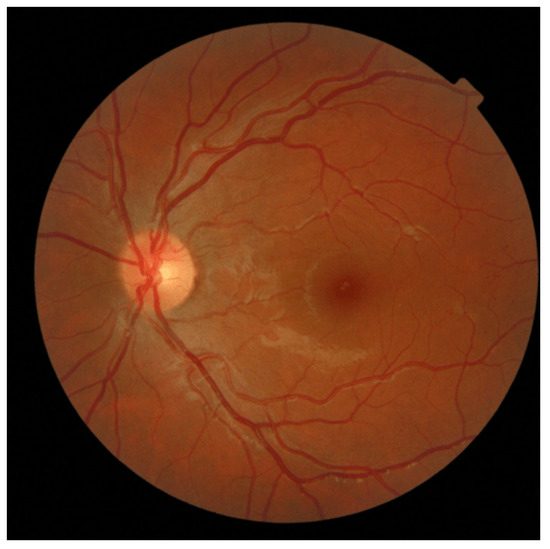

- Atypically Elongated Arteries and Normal Veins: In a subset of retinal images within the AV-Classification dataset, we encountered instances where the arteries displayed significant elongation while the veins retained a relatively normal appearance. This divergence in vascular morphology raises intriguing questions about the potential factors driving this asymmetry and may help physicians to efficiently diagnose retinal abnormalities. Figure 14 showcases that.

- Atypically Elongated Veins and Normal Arteries: On the other hand, a contrasting pattern was evident in certain other fundus images. The veins showcased noticeable elongation, while the arteries preserved a normal appearance. This polarized pattern adds another layer of complexity to our understanding of retinal vascular abnormalities; such cases may be signs of specific further diagnoses.

- Mixed Elongation: A subset of images revealed that both the arteries and veins exhibited varying degrees of elongation or, conversely, both appeared to be normal. This variability within individual retinas underscores the intricate nature of vascular architecture and emphasizes the need for a more holistic investigation; Figure 15 showcases this.